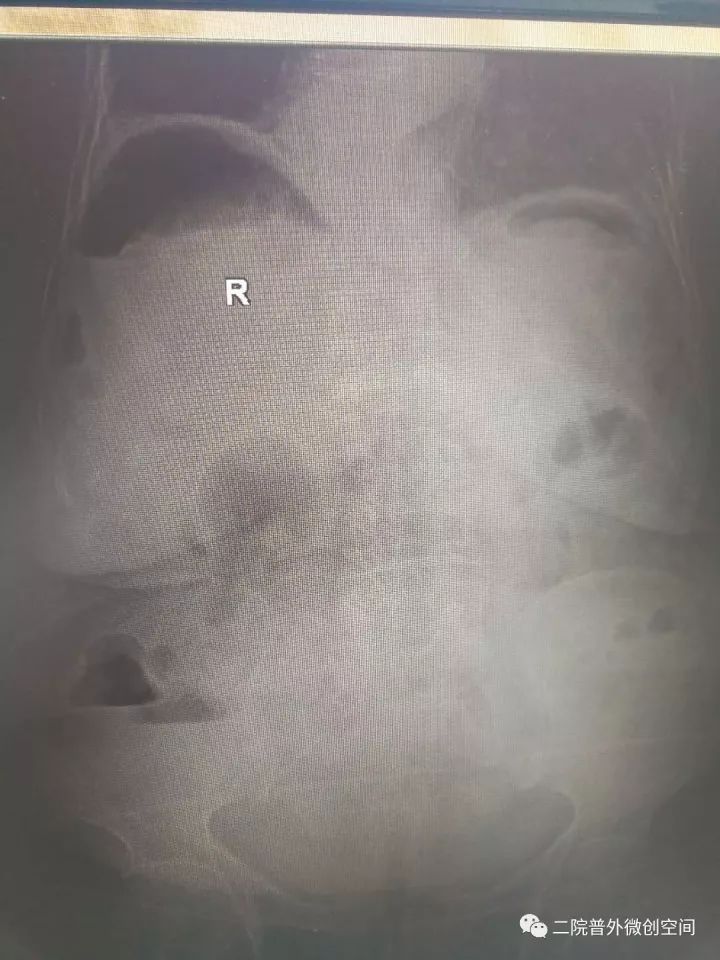

据悉,老奶奶月前摔伤而口服止痛药,2017年10月23日中午突然出现腹痛,逐渐加重,急到当地卫生院就诊,当地医生检视后斟酌“急腹症”急转夏邑县第二人民医院普外科。入院后经副主任医师井晓亮检查后斟酌消化道穿孔,治疗需手术治疗。

经过充分的术前准备,在麻醉科同事保驾护航下成功为患者施行了腹腔镜下胃穿孔修补术。麻醉及手术过程的艰难程度可想而知——低血压、低血氧、腹腔充满脓液,穿孔大......而这些,在井晓亮主任、谢龙医师、王天琪医师的精细操作下一一化解!